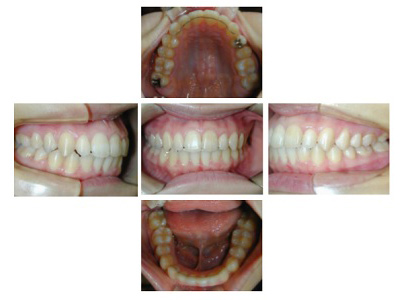

![]() |

各ステージで順調に治療がすすみました。

治療は順調に進みました。

犬歯の幅径が狭い事の対応として犬歯にダイレクトボンディングを行う、

下顎前歯のストリッピングを行うなどのプランを考えましたがその両方とも行うことなく動的治療を完了しました。

舌癖の存在は後戻りの大きな原因となりますので今後の保定治療でも注意が必要で、引き続き舌癖の改善を行います。

歯列矯正には副作用としてむし歯の発生、歯周病の悪化、歯肉退縮、歯根吸収、歯髄壊死などが起こる可能性があります。

治療期間:2年3ヶ月

治療費用:60万円